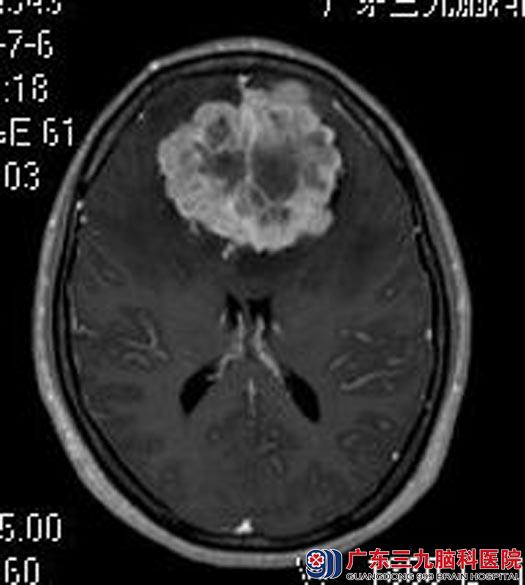

此后她的右眼视力逐渐下降,一个月前右眼视物不清,当地医院行头颅CT检查提示双侧额部大脑镰巨大占位。住院广东三九脑科医院综合神经外科。查体发现:陈女士右眼只剩光感,直接对光反射消失,间接对光反射迟钝,左眼视力4.2,直接对光反射迟钝,间接对光反射消失;行头颅MR检查提示:双侧额部镰旁占位性病变,约6.5cm×6.4cm×5.7cm,考虑脑膜瘤。

由鲁明主任主刀,在全麻下行双侧额部大脑镰旁巨大脑膜瘤切除术,术中见肿瘤质硬,包膜完整,血供一般,显微镜下行肿瘤全切,手术顺利,术后陈女士恢复很快,已康复出院。术后病理结果:纤维型脑膜瘤(WHO I级)。